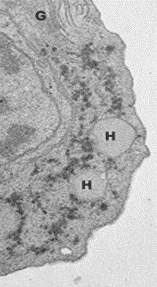

El hidrogenosoma hace que el piruvato (PYR) se convierta en dióxido de carbono (CO2) y acetato al producir hidrógeno molecular (H2) y poder convertir el ADP en ATP. Es por tanto la fuente de energía para este activo y movedizo protozoario flagelado, el más frecuente agente parasitario del ser humano. El hidrogenosoma resulta ser un orgánulo redondeado que está rodeado por una membrana y se encuentra en algunos protozoos flagelados y hasta en algunos hongos anaeróbicos, siendo por ello, orgánulo u organela, muy variable, que presumiblemente ha evolucionado a partir de protomitocondrias para producir hidrógeno molecular y ATP en condiciones anaeróbicas.

Sobre los hidrogenosomas se ha especulado de que evolucionaron a partir de las mitocondrias para proporcionar un mecanismo diferente para la síntesis anaeróbica de ATP utilizando el piruvato. La reacción da como resultado la producción de hidrógeno molecular, de donde esta organela recibe su nombre. Los hidrogenosomas miden entre 0,5 y 2 micrómetros y están rodeados por una unidad de membrana. Generalmente tienen forma redondeada o de mancuerna y se encuentran aislados o en grandes complejos apilados, desde 4 o 5 (llamados complejos juveniles) hasta 20 o más hidrogenosomas.